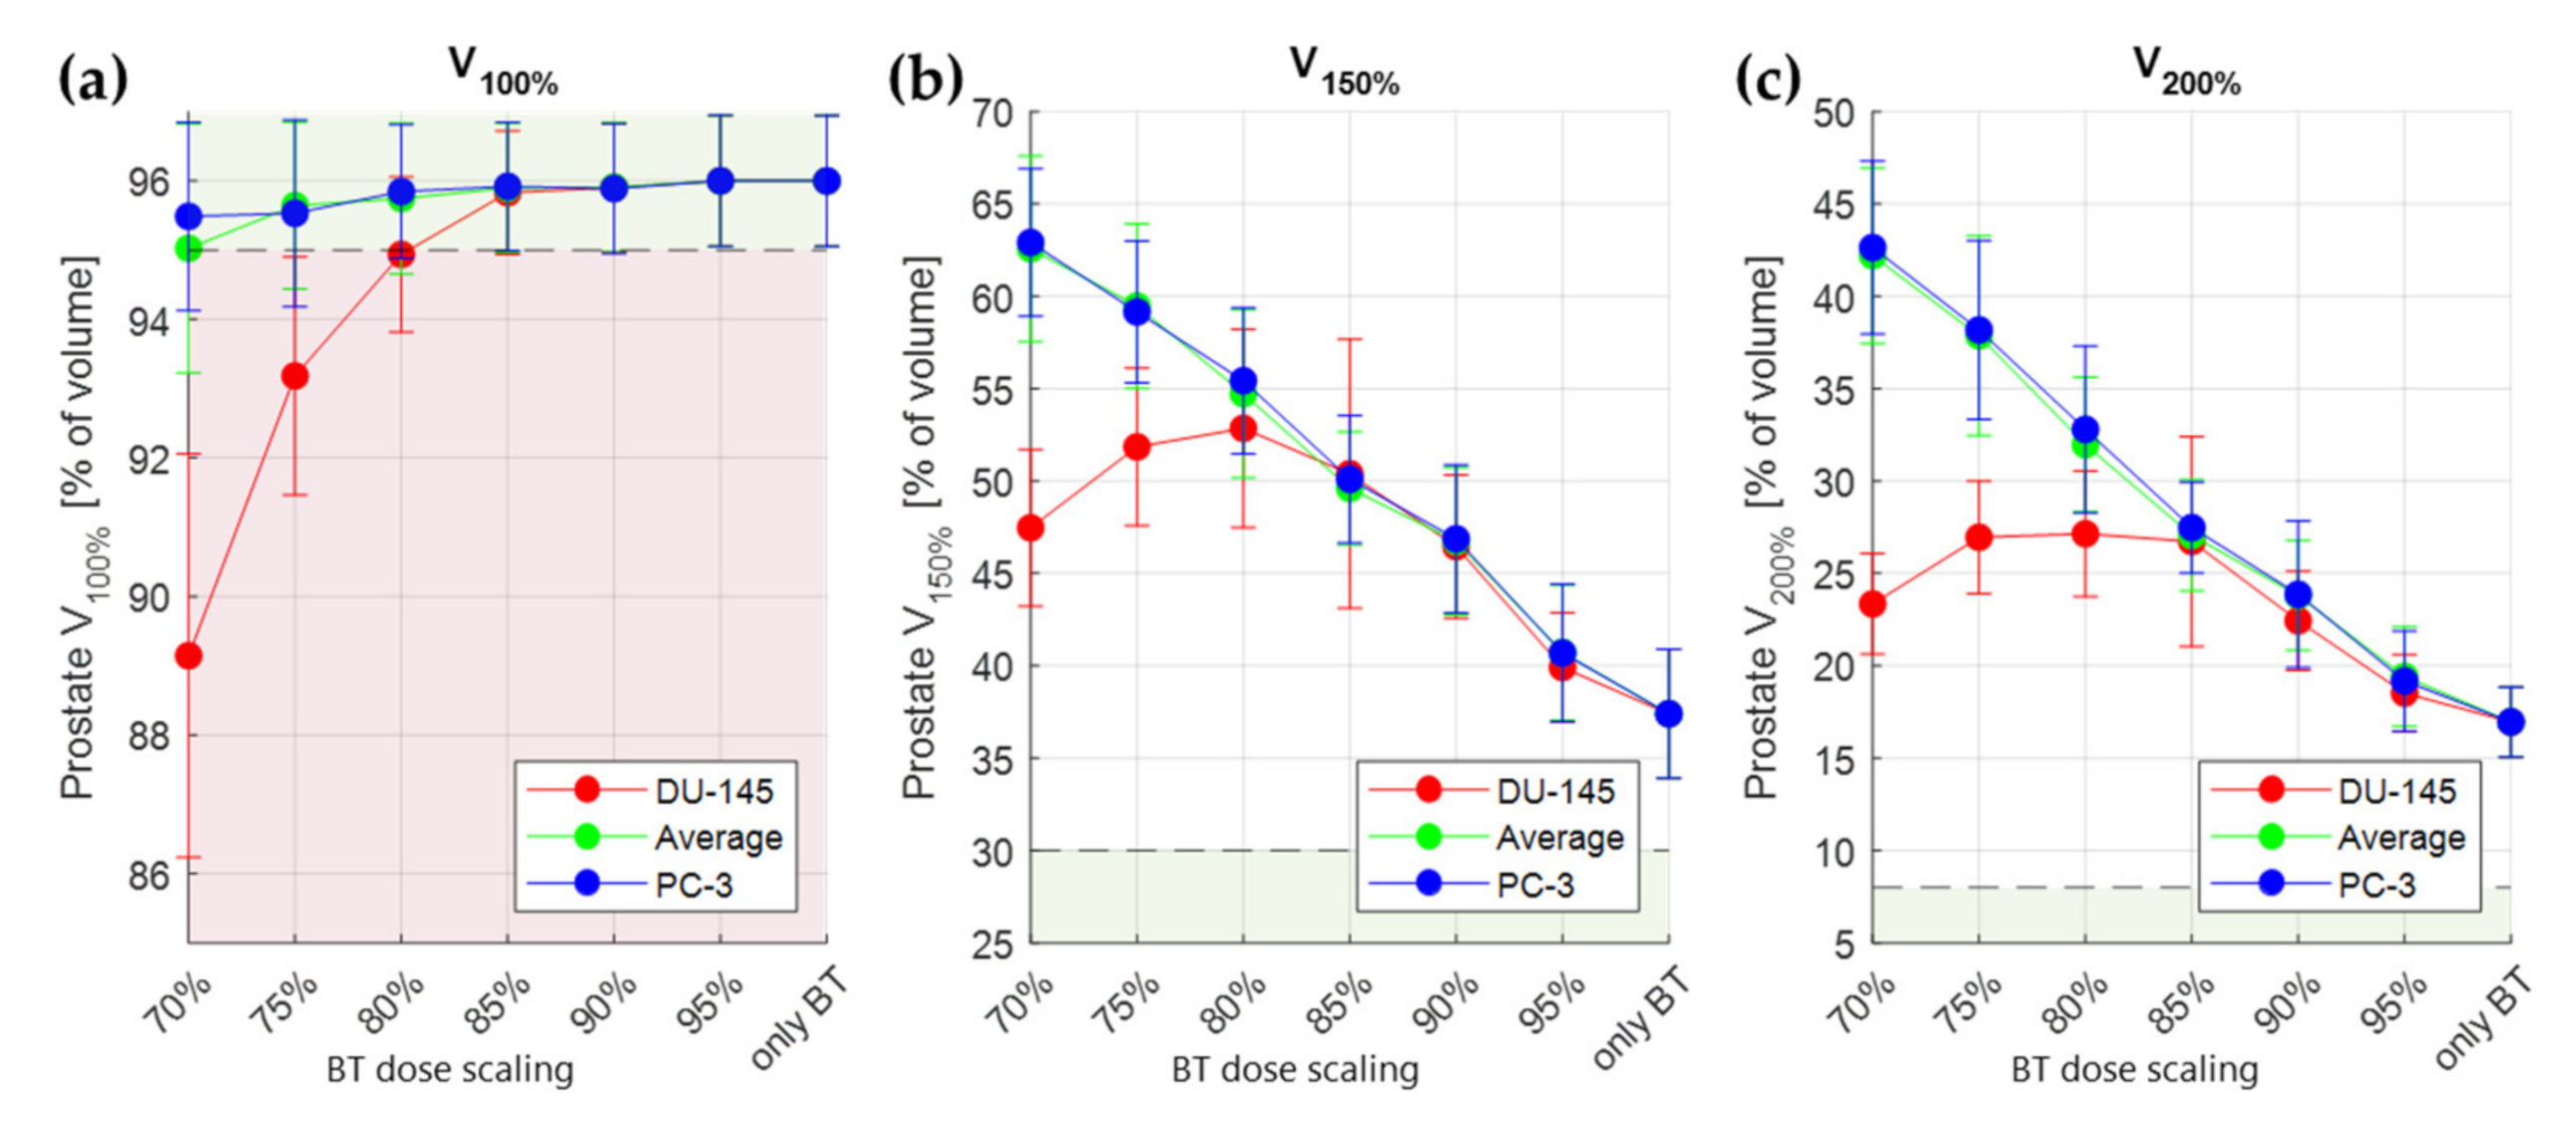

3.3. Treatment Planning Results

4. Discussion